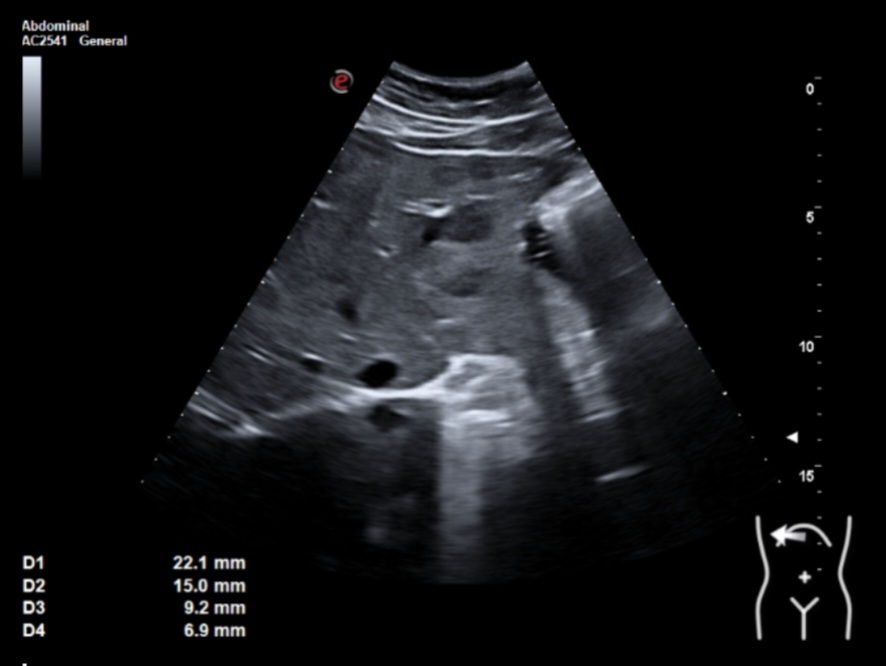

Ecografía clínica: múltiples lesiones en parénquima hepático bien delimitadas de hasta 2 cm, hipoecogénicas, en ambos lóbulos. Tamaño normal del hígado (15 cm) pero bordes obtusos. Vía biliar no dilatada. Vesícula alitiásica. Porta de calibre normal. Área pancreática no visualizada por gas intestinal. Ambos riñones normales. Vejiga vacía, no valorable.

Dados los hallazgos se solicitó ecografía reglada que informaba de múltiples lesiones hepáticas sospechosas y afectación adenopática infradiafragmática. Se recomendó completar estudio mediante TAC estadiaje.